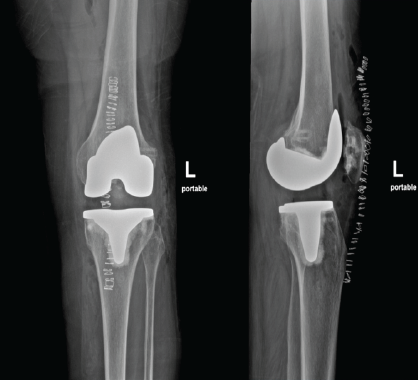

Post-graft fixation, intraoperative assessment confirmed restoration of posterolateral stability, with negative dial test and symmetric varus stress response. Patellar tracking remained central with no signs of maltracking or instability. The joint was closed in layers, and a hinged knee brace was applied. Postoperatively, the patient was managed with a hinged knee brace locked in extension for the initial 2 weeks. Early range of motion exercises was initiated from day 3, progressing cautiously under supervision to protect the reconstructed PLC. Weight-bearing was restricted to toe-touch ambulation for the first 4 weeks, followed by a gradual increase to full weight-bearing by week 8, aligned with improvement in quadriceps control and proprioceptive feedback. The physiotherapy protocol emphasized neuromuscular retraining, proprioceptive drills, and lateral chain strengthening, targeting the gluteal and biceps femoris musculature to restore posterolateral dynamic stability. Isometric quadriceps and hamstring co-contraction drills were introduced early, with closed-chain exercises phased in after 6 weeks (Fig. 2 and 5).

Figure 5: Immediate post-operative X-ray showing preserved joint and a well-balanced flexion extension gap.